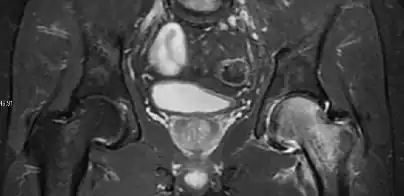

Radiological signs of transient osteoporosis of the hip include localized osteoporosis of the femoral head and neck (Figure 8). Nevertheless, final diagnosis has to be made with MRI to differentiate it from avascular necrosis and from insufficiency or stress fractures of the femoral head or neck. In case of AVN, radiographs can only demonstrate delayed or advanced signs. Staging according to Ficat classification ranges between normal appearance (stage I), slight increased density in the femoral head (stage II), subchondral collapse of the femoral head with or without “crescent” sign (stage III), and advanced collapse with secondary osteoarthritis (stage IV). In the case of stress or insufficiency fractures X-ray sensitivity has been proven to be much lower than MRI, which is currently the gold standard.[1]

Figure 8:

X-ray of a patient with transient osteoporosis of the left hip showing osteoporosis.[1]

Coronal stir imaging in transient osteoporosis, showing diffuse edema.[1]

Scintigraphy (A), sagittal T1 (B), and coronal PD fat sat of a patient with a subchondral fracture of the femoral head with convex shape to the articular surface.[1]

Coronal T1 of a patient with avascular necrosis of the femoral head.[1]